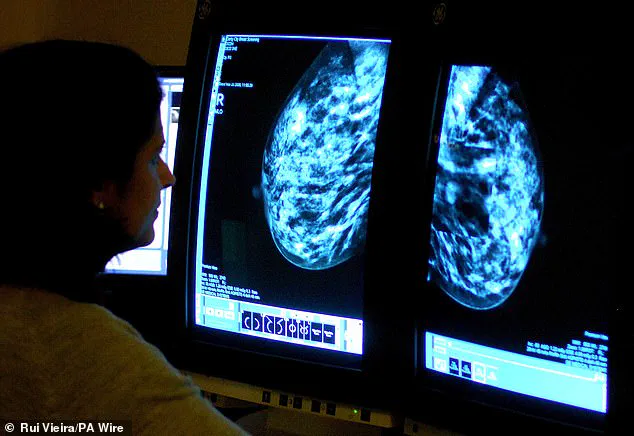

Now, preliminary studies indicate that tirzepatide may also play a role in slowing the growth of breast cancer tumours, a finding that could have profound implications for public health.

More importantly, the medication appeared to significantly slow the progression of breast cancer tumours.

These findings, while preliminary, suggest that tirzepatide may have a beneficial impact on breast cancer outcomes, particularly in individuals with obesity-associated cancer risks.